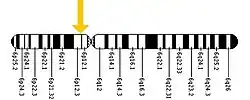

Caroli disease

Caroli disease (communicating cavernous ectasia, or congenital cystic dilatation of the intrahepatic biliary tree) is a rare inherited disorder characterized by cystic dilatation (or ectasia) of the bile ducts within the liver. There are two patterns of Caroli disease: focal or simple Caroli disease consists of abnormally widened bile ducts affecting an isolated portion of liver. The second form is more diffuse, and when associated with portal hypertension and congenital hepatic fibrosis, is often referred to as "Caroli syndrome".[2] The underlying differences between the two types are not well understood. Caroli disease is also associated with liver failure and polycystic kidney disease. The disease affects about one in 1,000,000 people, with more reported cases of Caroli syndrome than of Caroli disease.[3]

The cause appears to be genetic; the simple form is an autosomal dominant trait, while the complex form is an autosomal recessive trait.[2] Females are more prone to Caroli disease than males.[8] Family history may include kidney and liver disease due to the link between Caroli disease and ARPKD.[6] PKHD1, the gene linked to ARPKD, has been found mutated in patients with Caroli syndrome. PKHD1 is expressed primarily in the kidneys with lower levels in the liver, pancreas, and lungs, a pattern consistent with phenotype of the disease, which primarily affects the liver and kidneys.[2][6] The genetic basis for the difference between Caroli disease and Caroli syndrome has not been defined.